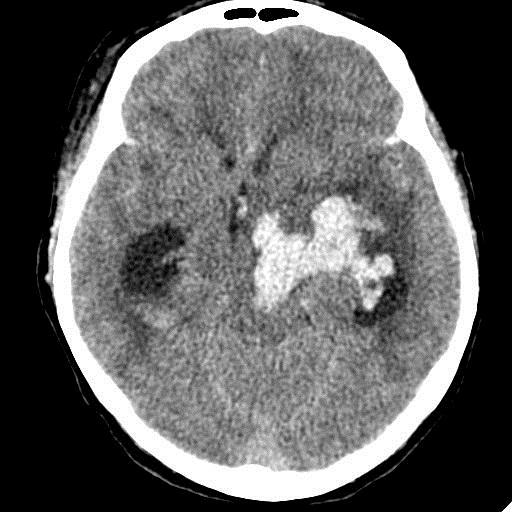

Острое внутримозговое кровоизлияние с выходом крови в желудочки (боковые - сгустки преимущественно в левом + эффект седиментации с горизонтальным уровнем жидкость\жидкость в задних рогах; сгустки крови в третьем желудочке, кровь в четвертом). Значительное увеличение височных рогов боковых желудочков - гидроцефалия. Смешение срединных структур вправо, отек белого вещества перивентрикулярно слева.

Довольно большие кровоизлияния в стволе мозга (что объясняет тяжесть состояния).

Дифференциация серого и белого в-ва сохраняется, хотя субарахноидальное пространство не прослеживается - проявление масс-эффекта, начальный этап отека мозга.

Остается вопрос по слегка гиперденсному (относительно серго вещества) однородному фокусу в левой лобной доле... и по причине кровоизлияния. Что касается последнего могу предположить патологию базилярной артерии (разрыв аневризмы?)... правда не вижу что-то крови в цистернах основания черепа.

Я написала отек мозга, острое массивное (около 100 мл только внутримозговое) смешанное кровоизлияние слева + в стволе, с прорывом и гемотампонадой желудочков, выраженной латеральной дислокацией (13 мм), менингиома? лобного полюса слева. Убедительных данных за опухоль, давшую кровоизлияние, не вижу, хотя такая мысль тоже была.  Контрастировать такую пациентку никто не будет, агонизирующая(.

У, сколько всего написано. Пока не пришла Nela, поучаствую и я. 1. Кровоизлияние в ткань мозга, а не в опухоль: а)не видно ткани опухоли; б) неясна первичная локализация опухоли (левые базальные ядра?!); в)нет перифокального отека вокруг предролагаемой опухоли, г) при опухолях прорывы в желудочки - редкость; 2) к поперечной дислокации добавил бы безесловную аксиальную: даже цистерна моста сужена, не говоря уже про обходную-четверохолмную и другие; 3) менингиома в левой лобной области, на мой взгляд, сомнительна (кстати, покажите ее пожалуйста), ИМХО - "игра" плотностей;  4) ///метастазы в сосудистые сплетения/// - это очень круто, но они не дали бы внутримозгового кровоизлияния, как и ///плексуспапилома///.

PS. Не очень понял про ///отек мозга///, есть снижение плотности (отек и ишемия) белого вещества левого полушария и задних отделов правого.

Массивное медиальное кровоизлияние с прорывом в желудочки. Кровоизлияние в ствол. Признаки вклинения. В лбу может что-то и есть, но это не принципиально. А может быть и отечные извилины. Смущает, что нет масс-эффекта.

Про отек: субарахноидальных щелей совсем нет, по белому веществу и в стволе снижение плотности, извилины утолщены, серое вещество на этом фоне выглядит более светлым, толстым, подушкообразным.

Причина таких кровоизлияний, как правило, гипертензия и атеросклероз.